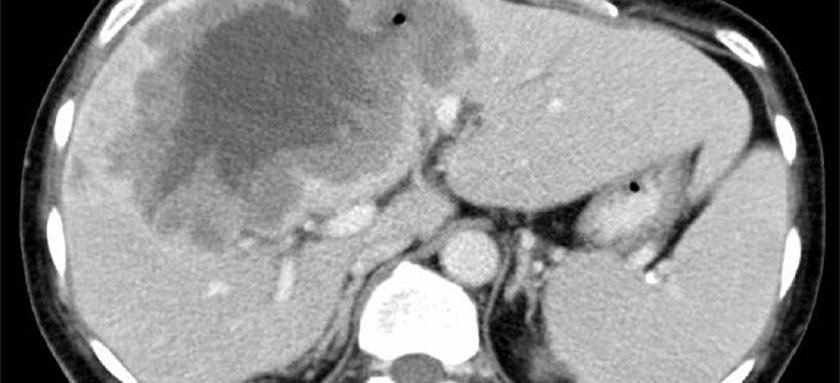

Karaciğer metastazı tedavisi

• Metastazın sayı, büyüklüğü ve yerleşimi